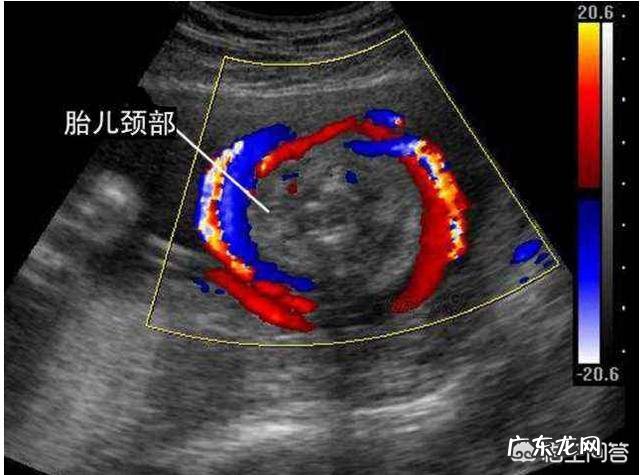

脐带绕颈一般是1-3周,如果脐带绕颈,那么胎儿的颈部会有U形或者是W形的血流 。B超单会备注绕颈一周或者是数周 。